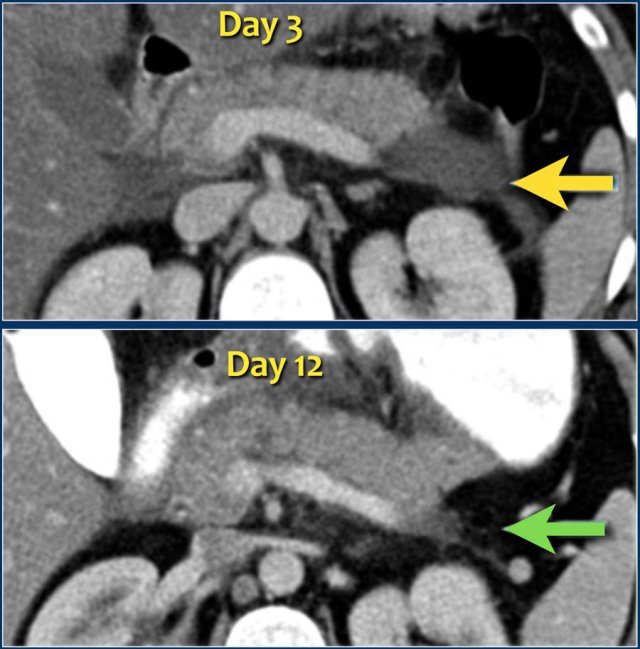

The images show spontaneous regression of an acute peripancreatic fluid collection (APFC).